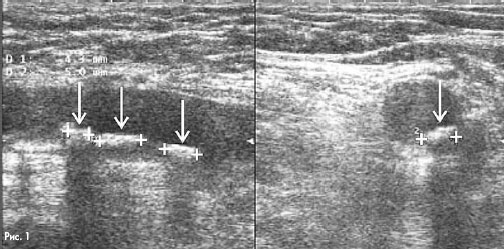

На рис.1 в продольном и поперечном сечениях сканирования выявляются 3 атеросклеротические бляшки диаметром от 4,5 -5,0 мм. Стрелками указаны бляшки, а крестиками - их границы.